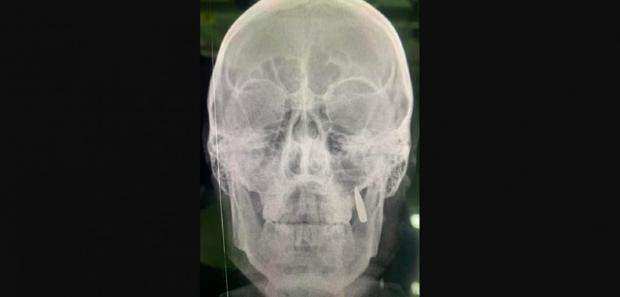

За її словами, при цьому боєць переживав, що згодом треба буде до стоматолога їхати. “Робимо рентген, замість двох зубів у щелепі застрягла куля. Ну так собі імплант”, – написала Корчинська.

Також вона показала рентгенівський знімок бійця, де видно кулю, яка застрягла у щелепі.